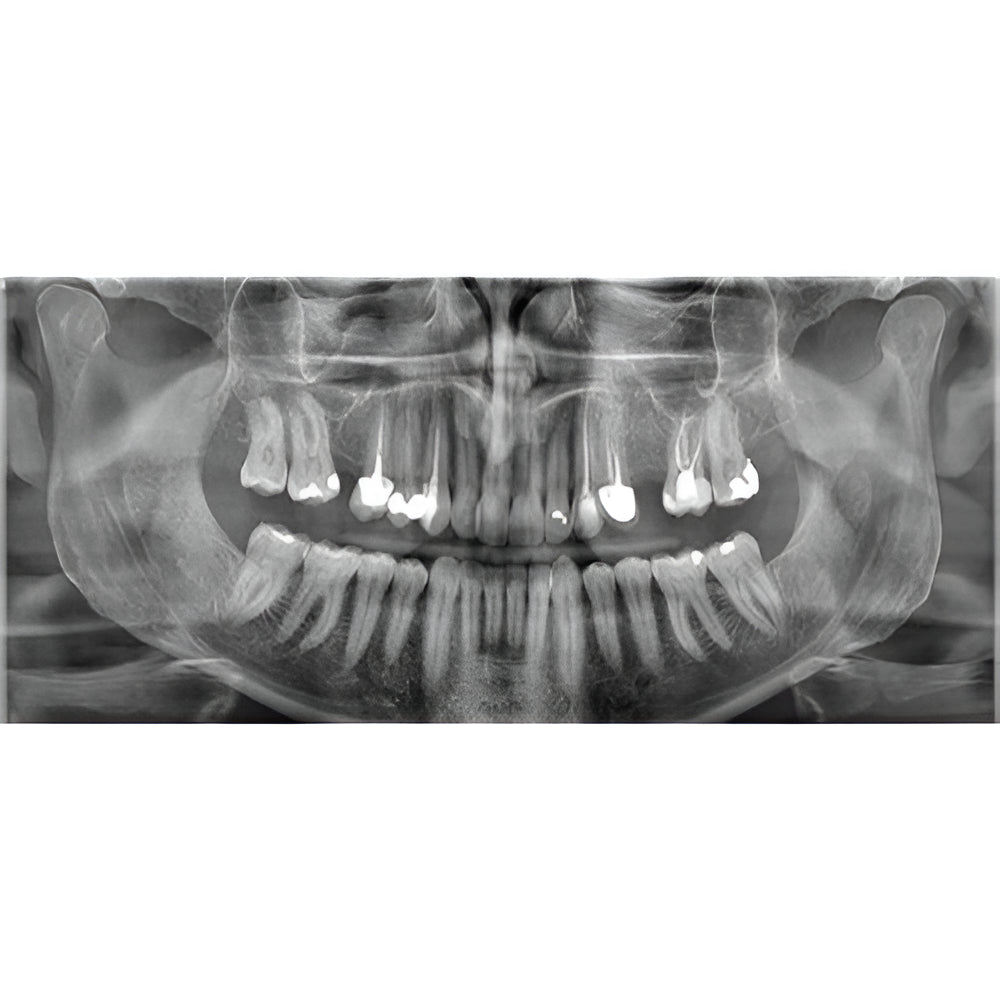

Enter a world of crystal-clear 3D images with the CS 8200 3D Access-a CBCT system that’s state-of-the-art, but intuitive and easy to use, taking your dental practice to the next level. Enjoy CBCT imaging that’s easier than you think and built on an open platform so that you can activate your future practice here and now.

- Easy, advanced CBCT imaging now available to everyone

- Versatile 4-in-1 solution ideal to expand treatment options